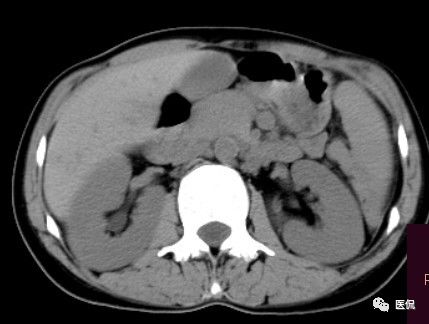

女 40岁 ,10年前做个剖腹产术。之后到现在一直感觉肚子疼,去很多医院做检查 诊断肠结核,经过反复抗结核治疗。病人10年瘦了几十斤。

腹腔内残留的纱布在人体内引起渗出或液化坏死并纤维包裹形成异物性脓肿(纱布瘤)。纱布瘤的影像特点:圆形或卵圆形肿块,较大,有完整包膜,薄壁,较少的情况下为厚壁,边界较完整,增强后薄膜可以持续强化。不同时期的纱布瘤可以有不同表现:早期(10个月或半年内)多表现为蜂窝状;2~5年内一般表现为囊性飘带状;10~20年之后则为实性软组织密度,包膜钙化呈钙化网状结构。手术过程中残留在人体内的医用纱布所形成的肿瘤样病变。

纱布团遗留腹腔后,首先由大网膜及邻近肠管将其紧密粘连并包裹,自肠管与纱布团粘连处开始逐渐向周围扩展产生纤维结缔组织包膜直至完全包住纱布团,该包膜血管丰富,充血明显,随时间延长逐渐向纱布团网眼内生长,使包膜逐渐增厚。机体还通过在包膜内产生大量异物巨细胞来围歼异物纱线,使包膜内侧形成脓肿。当包膜完全形成后,肠管与纱布团的粘连变的疏松,此时纱布团具有了一定的活动度。

腹腔内遗留纱布团的影像学表现,以B超较具特征性,其主要表现为:腹腔或盆腔内特殊率减的黑色包块,后方伴有扇形衰减的声影,上窄下宽,好似一“黑色大布”,早期包块内含有不规则光团或光点,随时间延长有缩小或消失,为纱布团内气体。CT的优势在于早期常表现为软组织密度的肿块,其内可见多少不等的气泡,随时间的延长气泡逐渐被吸收减少至消失,增强扫描可见包膜不同程度强化而内容物无强化。熟悉其影像学表现,可在术前作出明确诊断。